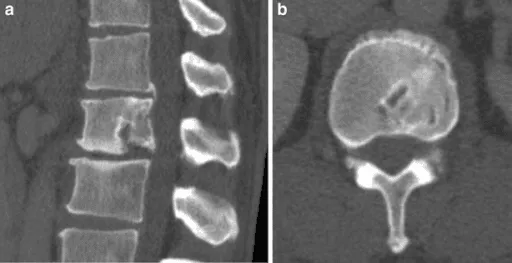

CT scans showing a spine fracture in sagittal (a) and axial (b) views.

Spinal Instability

Removal of stabilizing bone can lead to spinal instability requiring fusion.